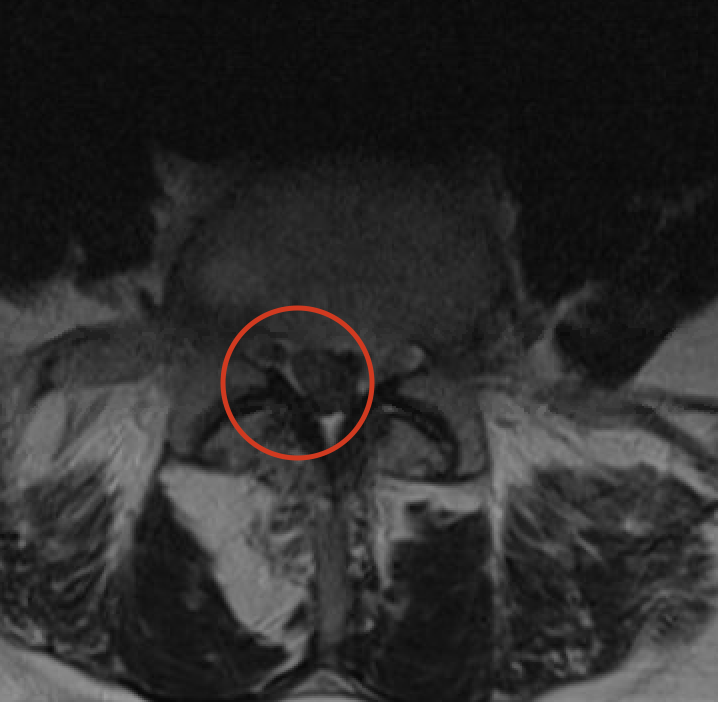

Het ideale onderzoek is een NMR (=MRI). Het levert ons de beste beelden en gebruikt geen nadelige X-stralen. Soms wordt ook een CT scan van de lumbale wervelzuil gevraagd.

Discus hernia betekent in het Nederlands breuk (= hernia) van de tussenwervelschijf (= discus). Een tussenwervelschijf bestaat immers uit een centraal zacht gedeelte en een omliggende ring. De breuk ontstaat in de buitenste ring waardoor het zachte gedeelte naar achter schuift en druk geeft op het ruggenmerg of zenuwen. Hierdoor kan pijn in het been ontstaan (in de volksmond omschreven als ischias, sciatique of ingeklemde zenuw) wat het typische symptoom is van een hernia in de lage rug. Een hernia kan ook aanwezig zijn zonder symptomen en moet dan ook niet verder behandeld worden.

Microdiscectomie is het verwijderen van een hernia thv de lage rug langs rugzijde via microscoop waarbij gebruik gemaakt wordt van een minimale insnede.

Er wordt een insnede van ongeveer 2 á 3 cm gemaakt in de middellijn van je rug. De rugspieren aan de zijde van de hernia worden losgemaakt. Tussen de 2 wervelbogen bevindt zich een ligament welke deels wordt verwijderd. Nu bevinden we ons in het ruggenmergkanaal. De zenuw wordt opgezocht en opzij gehouden. De hernia wordt nu met een kleine tang verwijderd. Rond de zenuw en ruggenmerg wordt een gel aangebracht die verkleving van littekenweefsel aan de zenuw en ruggenmerg voorkomt. Deze gel verdwijnt spontaan na 1 maand.